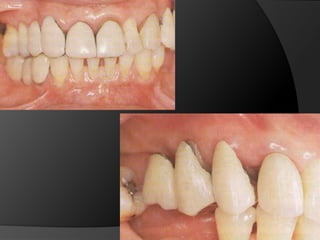

Diagnóstico y Planificación MultidisciplinariaEl examen clínico y la historia clínica nos darán información sobre los factores locales y sistémicos que pueden tener gran influencia en la obtención de un pronóstico para el tratamiento propuesto

Diagnóstico y Planificación MultidisciplinariaHistoria ClínicaAnamnesisFotografía clínica Montaje modelos de estudioEncerados DiagnósticosEvaluación Radiográfica Radiografías PeriapicalesRadiografía PanorámicaEvaluación DentalEvaluación PeriodontalEvaluación EndodónticaEvaluación OclusalEvaluación Articular?

El análisis para seleccionar la ubicación de la línea de terminación se enfoca en 2 componentes:Estética vs HigieneExtensión mínima dentro del surco gingivalDisimular la zona de asentamientoFacilitar la higiene del pacienteNecesidad de aumentar la retención y estabilidadLínea de Sonrisa

PRINCIPIOS ESTÉTICOSRestauraciones con forma, contorno y color adecuados